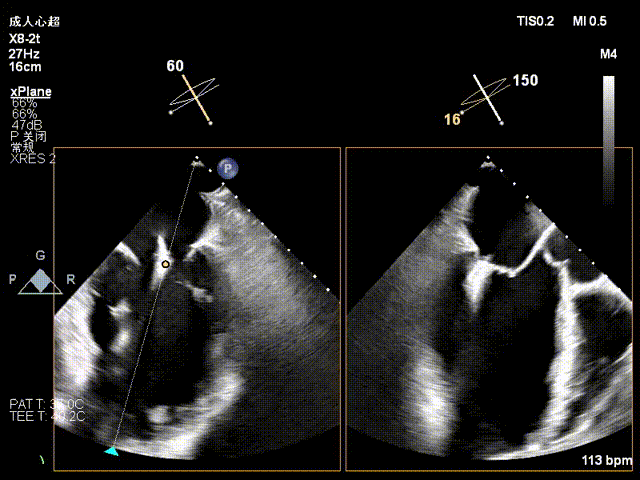

术前X-plane

术前3D切面

2、后叶室性栓系,质地菲薄,瓣叶精准捕获的难度增大;

手术中,团队精准实施房间隔穿刺(穿刺点靠后靠上,高度达 4.5cm),依托 DragonFly™器械三段式导管设计与刻度化调节优势,使器械精确抵达中央 2 区。在 X-plane 切面引导下,将夹子轴向 M\L 垂直瓣环平面、A\P 调整至 12 点钟方向,经弹道测试指向心尖后,采用 “优先独立捕获前叶、再针对性解决栓系后叶” 的操作思路,逐步关闭夹子释放瓣叶张力,有效规避瓣叶撕裂风险,成功完成单枚长宽二尖瓣夹植入。